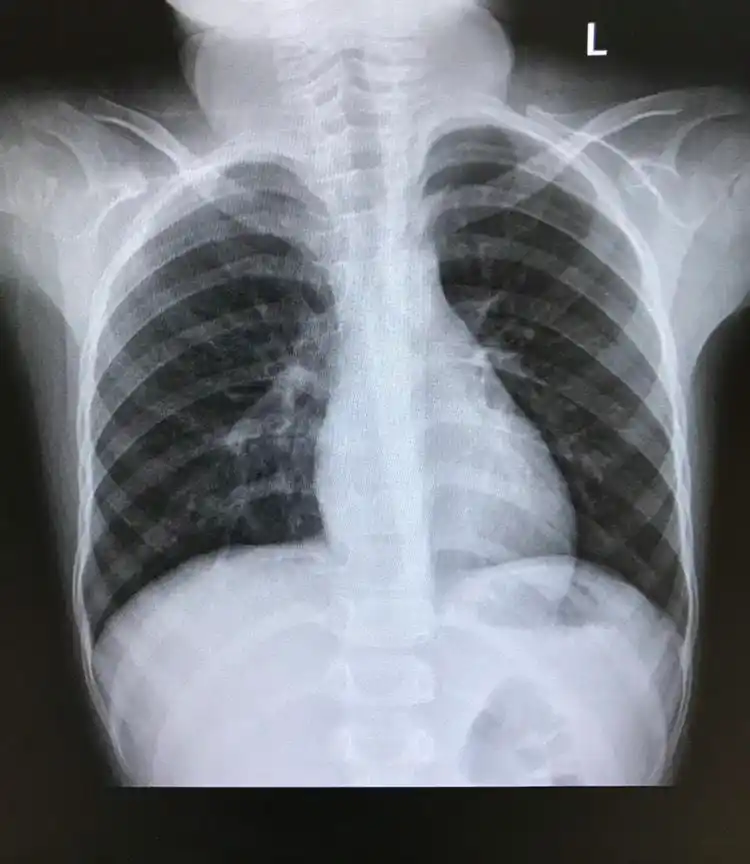

标准胸部x线摄影图片